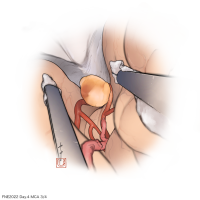

FEN2022シリーズ